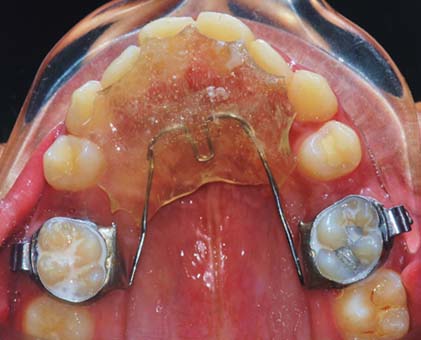

A Wilson’s 3D lingual arch was fabricated, activated and inserted into the lower arch, after the extraction of the second premolars, in order to upright the lingually tipped mandibular molar and also to correct the scissor bite on left side [Table/Fig-2].

Insertion of the 3D Lingual arch immediately after the extraction of the second premolars.